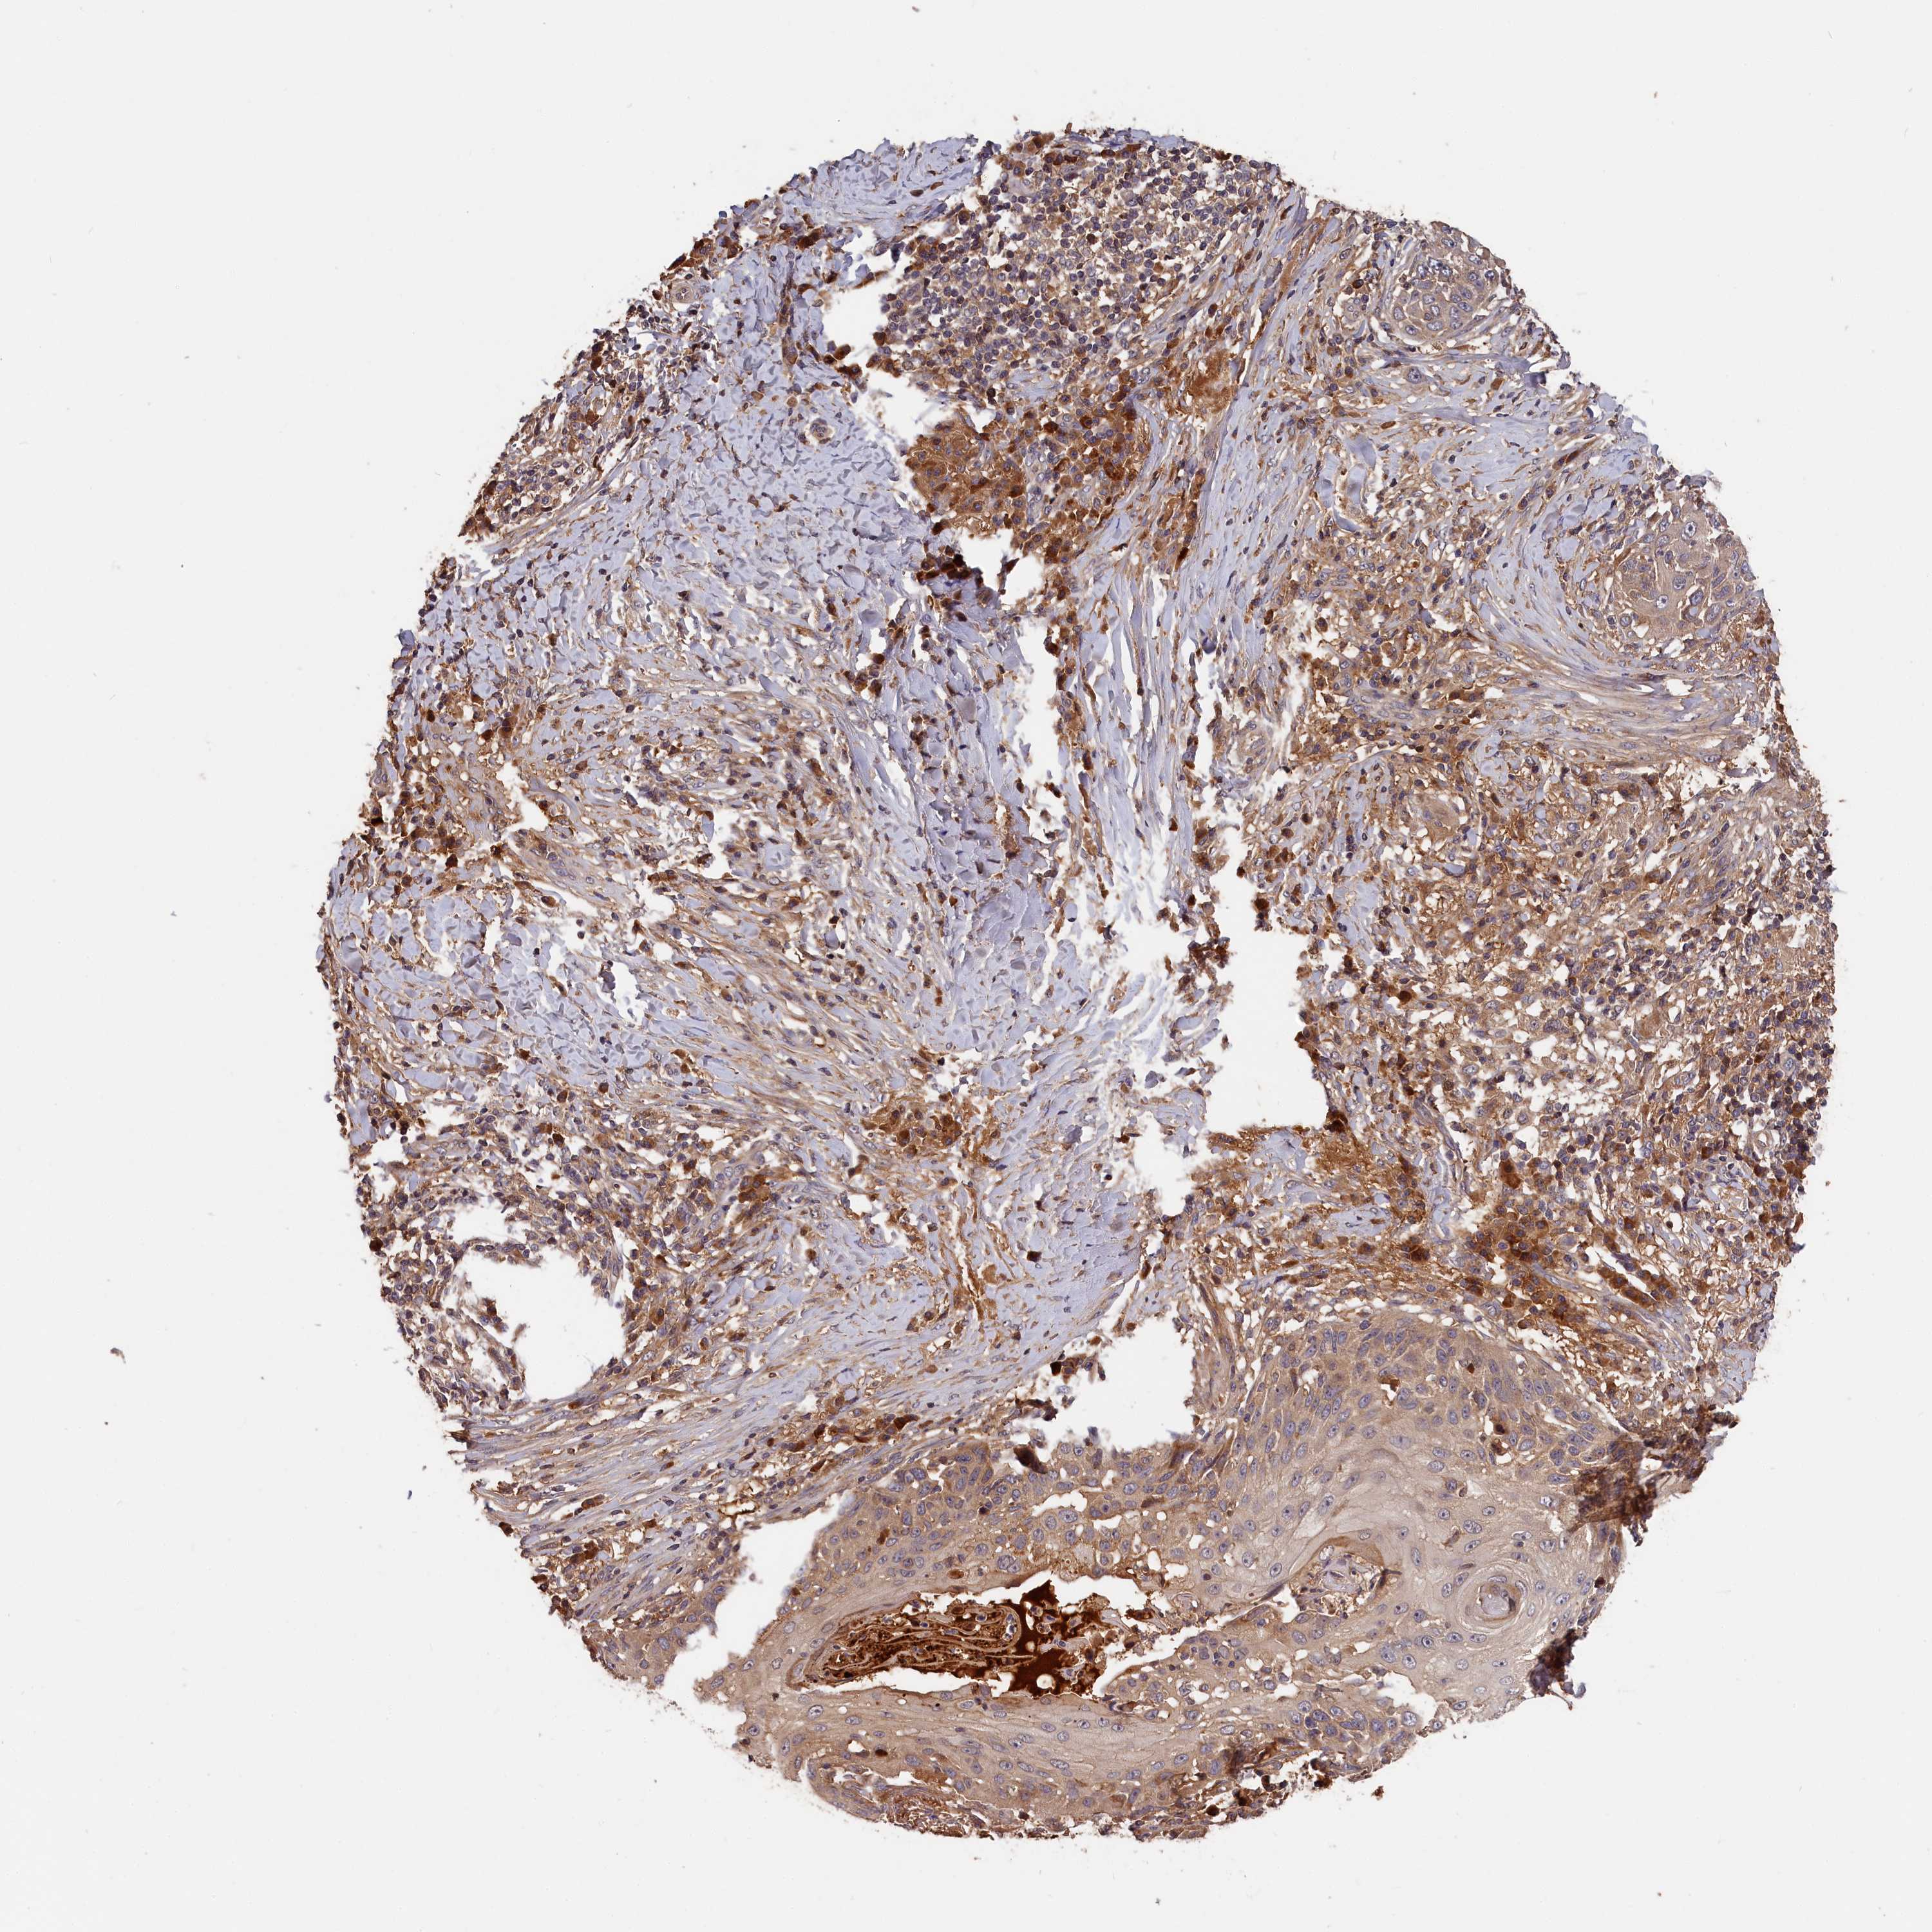

SKIN CANCER - Protein expressioni

A mouse-over function shows sample information and annotation data. Click on an image to view it in a full screen mode. Samples can be filtered based on level of antibody staining by selecting one or several of the following categories: high, medium, low and not detected. The assay and annotation is described here.

Antibody stainingi

Antibody staining in the annotated cell types in the current human tissue is reported as not detected, low, medium, or high, based on conventional immunohistochemistry profiling in selected tissues. This score is based on the combination of the staining intensity and fraction of stained cells.

Each image is clickable and will lead to virtual microscopy that enables deeper exploration of all samples and also displays staining intensity scores, fraction scores and subcellular localization as well as patient and tissue information for each sample.

Antibody HPA041639

Antibody HPA042049

Squamous cell carcinoma, NOS